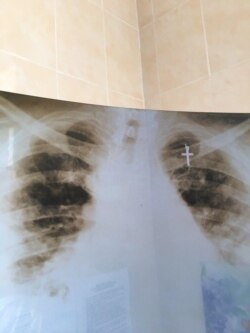

«Перше, що ми їм даємо – це кисень. Друге, що ми їм даємо – це препарати, які запобігають тромбоутворенню. Це не класична вірусна пневмонія, до якої ми звикли. Це мілкий пневмоніт судин легень, всі легені в мікротромбах. І тільки потім ми додаємо антибіотики, коли є доведена бактеріальна інфекція. Для «ковідних» антибіотики – це як при перитоніті грілкою гріти живіт», – говорить лікарка. В лікарні дотримуються останньої версії протоколу лікування COVID-19 від МОЗ.

Свердлюк проводить аналогію – вірус імітує отруєння чадним газом. Він зв’язується із гемоглобіном, утворюючи токсичний гемоглобін, за рахунок чого легені повністю уражаються мікротромбами. Тому потрібен кисень, щоб очистити отруєння організму.

Знімок легень пацієнта із коронавірусом